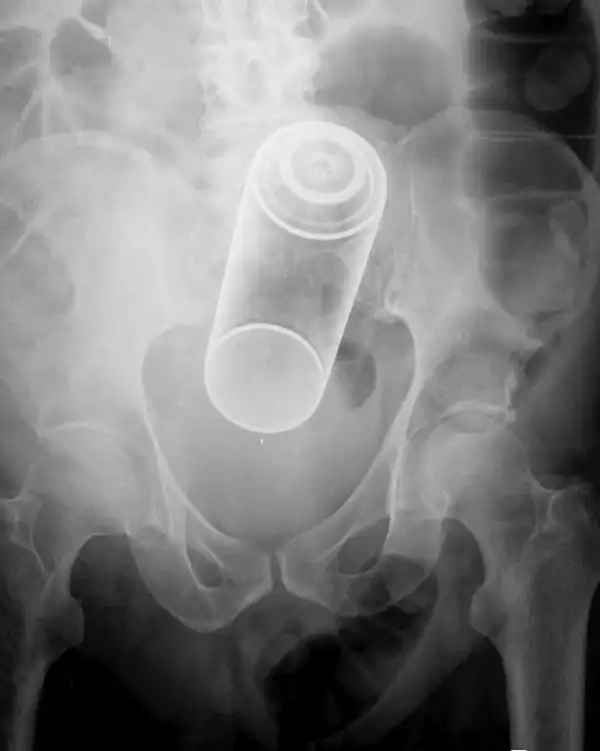

Врачебные находки в интимных местах

Или как впихнуть невпихуемое :lol: